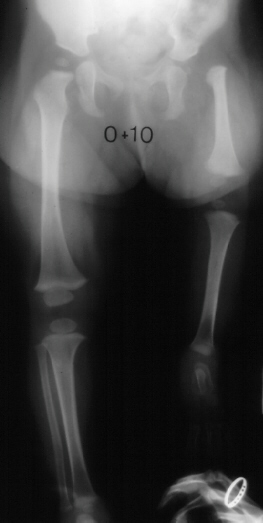

If

the foot is at the level of the knee the treatment of choice is

a Syme amputation of the foot.